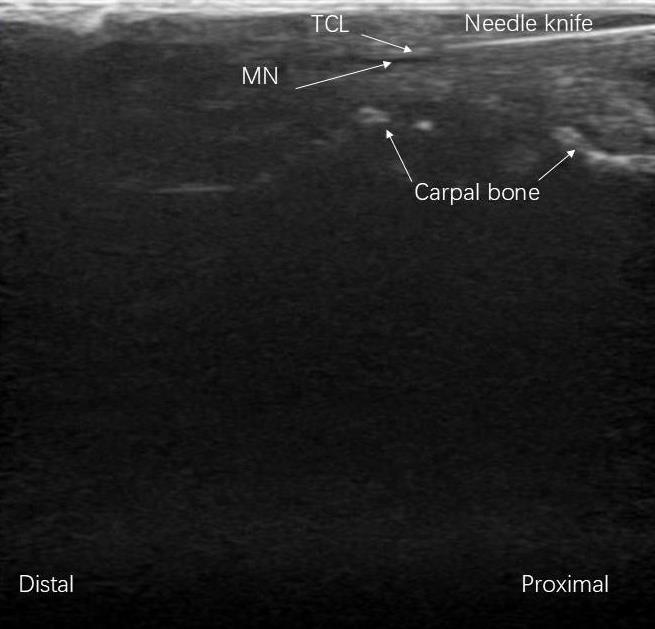

Fig.1 Procedure of ultrasound-guided needle knife release of the transverse carpal ligament (TCL) for treatment of carpal tunnel syndrome (CTS) in rabbits (long axis, longitudinal section). MN: Median nerve.